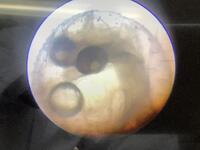

5年生理科 メダカの発生の観察ラストその2

5年生理科でメダカの卵を観察しました。新たに入荷した卵はいろいろなステージが揃い見応えがありました。